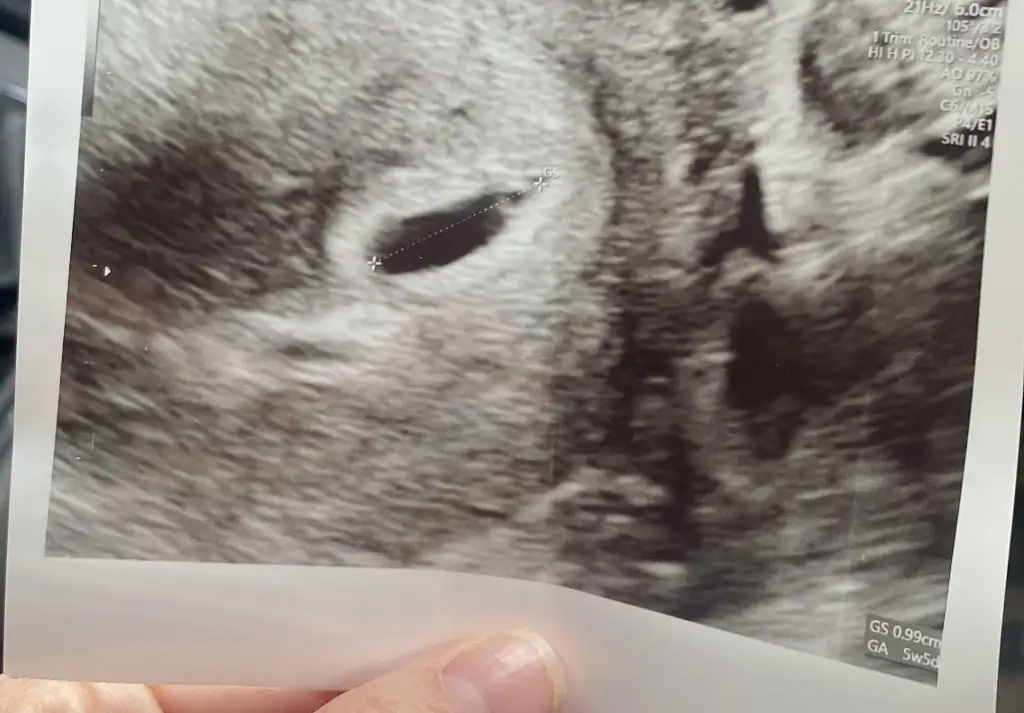

0.99 cm yazıyor kuzum. Normalde 5 de gitmiştim sata göre. Doktor kese götürüne göre tahminen 5+5 gibi dediKaç mm dedi doktor ? Bence gayet normal kuzum her kese farklıdır

Senin kesen benimkinden büyük kalp atışı için ne zaman gidiceksin0.99 cm yazıyor kuzum. Normalde 5 de gitmiştim sata göre. Doktor kese götürüne göre tahminen 5+5 gibi dedi